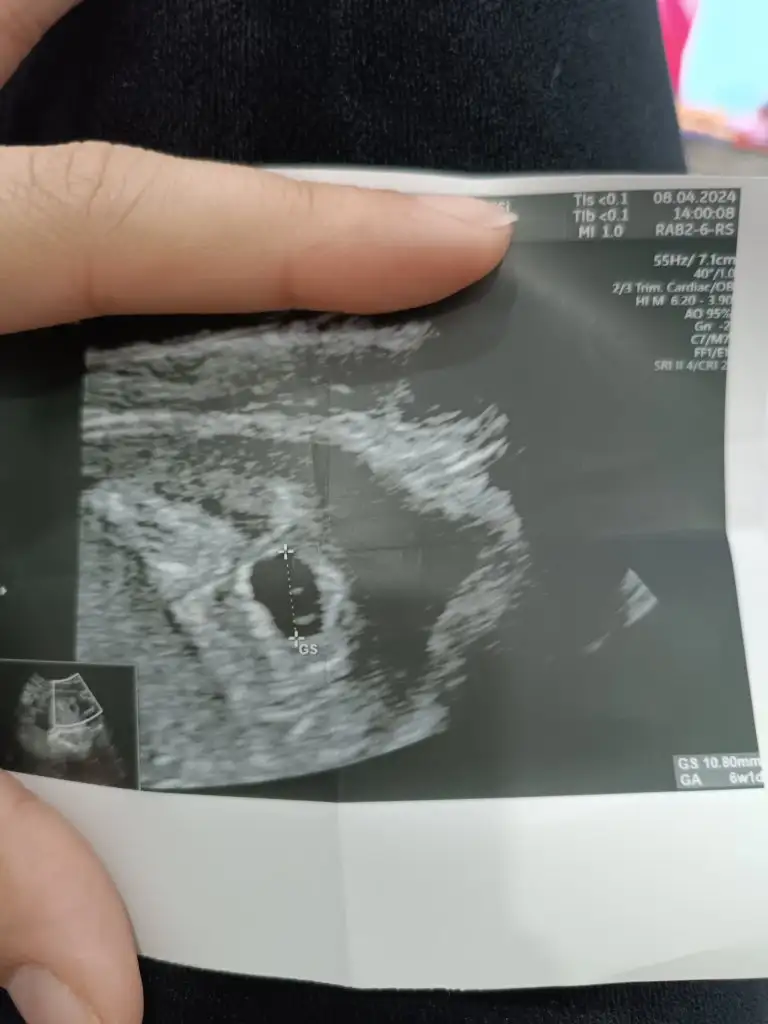

Olması gerektiği gibi çıkmış canımİnşallah güzel haberler alırız. Benimde son adet tarihim 4 mart fakat ultrasona göre 5 hafta 3 günlük çıktı beta hcg çok yükselmişti bir anda sanırım onunlada alao

Merhaba ultrason görüntüsü var mı acabaKızlar yolk sac ne zaman gözükür diye dün sormuştum bir cevap alamamıştım bugün 5+0 kese içinde karından ultrason ile yolk sacı gördük 6. Haftaya kadar görememe olabiliyormuş bilginiz olsun merh

6 hafta 4 günSizin ne kadarlık tahmineninşallah güzelce gider her şey